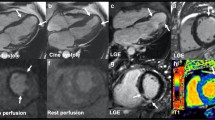

OS-CMR provides information on myocardial oxygenation and can obtain quantitative markers of myocardial ischemia and microvascular dysfunction across a number of disease states (Fig 3).

Oxygenation-sensitive CMR (OS-CMR) in a heart failure patient demonstrating a globally impaired myocardial oxygenation reserve, in a patient with coronary artery disease with a significant left anterior descending (LAD) lesion with a fractional flow reserve of 0.58 demonstrating regionally impaired myocardial oxygenation, and a healthy volunteer demonstrating a globally increased myocardial oxygenation response to a combined vasoactive breathing maneuver.